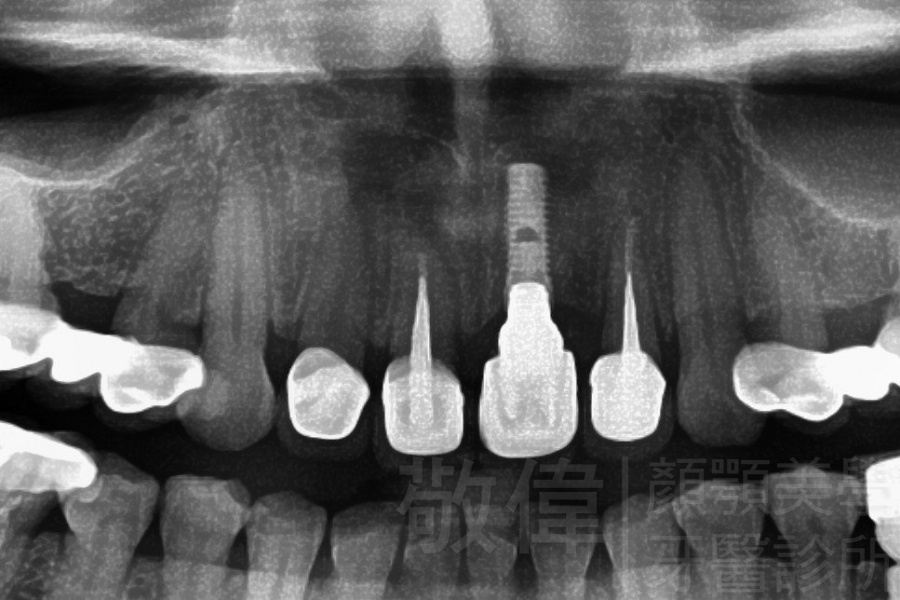

人工植牙/上顎前牙植牙重建

治療前-缺上排前牙   治療後

治療前-全口X光   治療後-全口X光